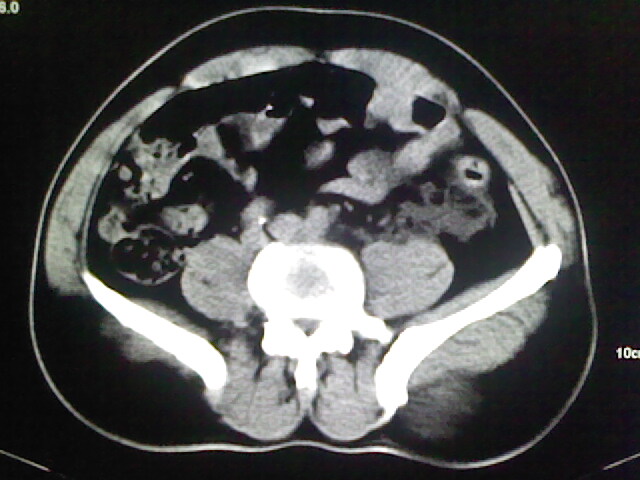

以下是引用zsl6918在2009-2-7 7:29:00的发言:[br]请提供介入的方式方法,肾及输尿管改变考虑与介入损伤有关,漏了,尿液外渗。

以下是引用余辉在2009-2-7 8:27:00的发言:[br]可能是硬化剂烧穿囊壁进入肾盂输尿管了,尿漏。不除外介入或碎石术后合并感染[br]患者术后怀疑结石,接着就碎石了?就怀疑没有确诊吗?碎石用的什么方法?气压弹道还是体外超声?如果这样的话责任人都难找

以下是引用随光逐影在2009-2-7 8:46:00的发言:[br]支持3楼意见。[br]另:不排除左肾及肾周感染可能。